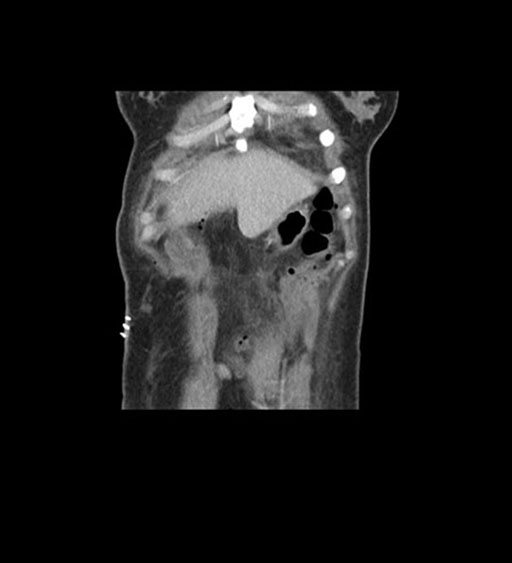

Imaging Analysis

Look through the patient's CT scan to identify any areas of concern for the necessary procedure.

Coronal Arterial

Coronal Venous

Based on initial findings, which issue(s) would you be most concerned about?